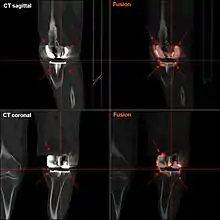

Loosening

Loosening of the prosthesis can be indicated on X-ray by thin radiolucent spaces around the implant, or more obviously by implant displacement.[49]

Knee replacement is routinely evaluated by X-ray, including the following measures: